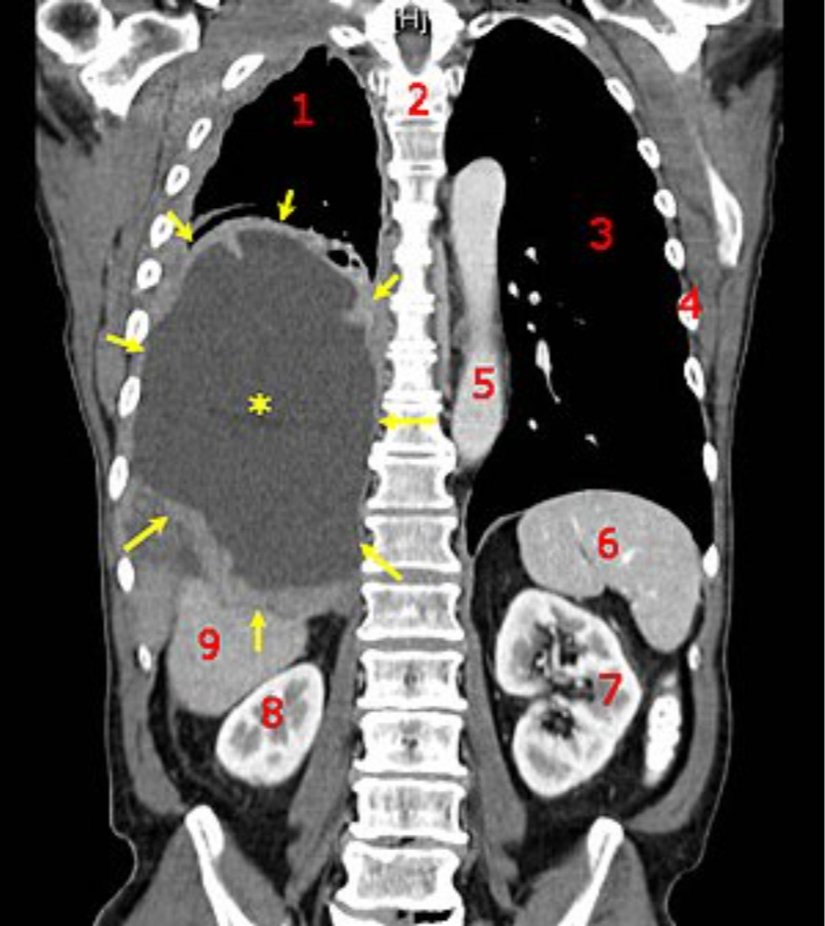

Kötü huylu (malign) tümörler ise kanser olarak adlandırılır. Komşu organ ve dokulara yayılırlar, kemik doku ile karşılaştıklarında onu dahi eritirler (rezorbsiyon). Sınırları belirsizdir. Malign tümörü oluşturan hücreler o kadar farklılaşmışlardır ki orijinlerinin ne olduğunu söylemek imkânsızdır. Lenf ve kan yoluyla uzak organlara da yayılırlar.